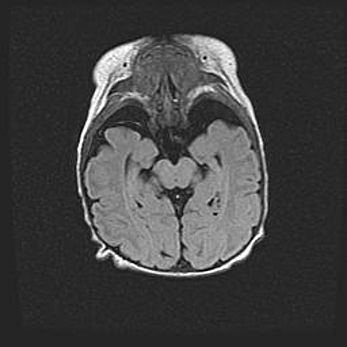

Неполная лизэнцефалия (пахигирия). Открытая гидроцефалия.

Возраст: 17 дней

Вес: 3110 г

Пол: мужской

Окружность головы: 33,5 см

Срок гестации: 35-36 недель

Лизэнцефалия—недоразвитие корковой пластинки и мозговых извилин в результате нарушения миграции нейронов коры. Поверхность мозговых полушарий гладкая. Микроскопически выявляется отсутствие нормальных слоев коры и скопление групп нейронов в подкорковом белом веществе.

Пахигирия—уменьшение числа вторичных извилин. В пораженном полушарии нервные клетки образуют толстый недифференцированный слой с неправильно расположенными нервными волокнами и группами гетеротопных клеток. Нервные клетки незрелые. Белое вещество истончено. При этом нередко аномально развит корково-спинномозговой путь.